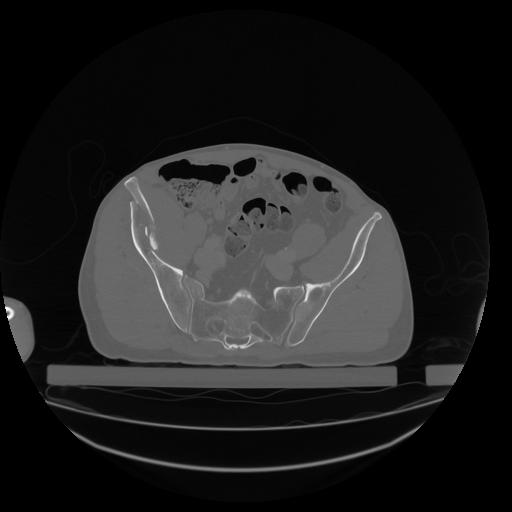

34 CUERPO,CE,Vol,1.0,CUERPO,,